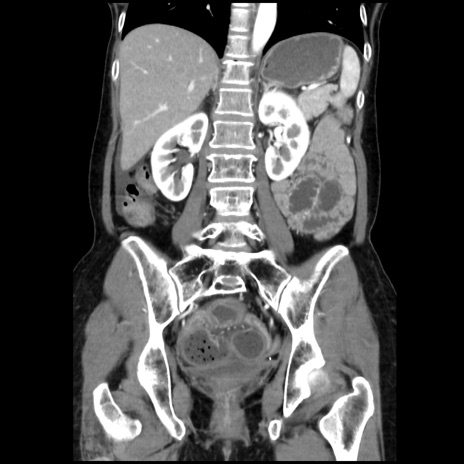

症例32(冠状断像)

【症例】40歳代 女性

【主訴】上腹部痛、嘔気・嘔吐

【現病歴】約9時間前頃から急に上腹部痛、嘔気、嘔吐が出現。改善しないため救急要請。

【既往歴】子宮頚癌(広汎子宮全摘術、放射線療法)、腸閉塞

【身体所見】腹部:平坦、軟、腸雑音亢進、上腹部を中心に腹部全体に圧痛あり。

【データ】WBC 8400、CRP 0.03